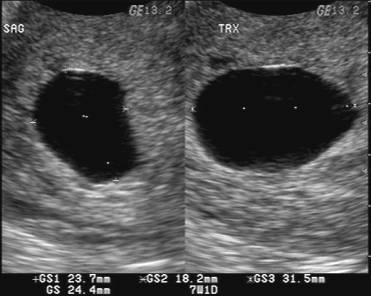

Nab V Twitter Hamil Anggur Itu Kalo Di Usg Yg Keliatan Cuma Kantong Janin Dan Mirip Bubble2 Gitu Gaada Isinya Pict 1 Itu Hamil Anggur Pict 2 Hamil Beneran Https T Co Sn6fcpv6wd

Nab V Twitter Hamil Anggur Itu Kalo Di Usg Yg Keliatan Cuma Kantong Janin Dan Mirip Bubble2 Gitu Gaada Isinya Pict 1 Itu Hamil Anggur Pict 2 Hamil Beneran Https T Co Sn6fcpv6wd